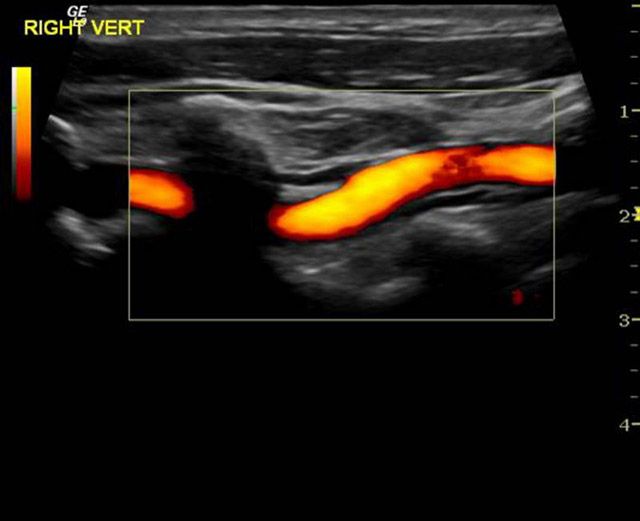

ΕΓΧΡΩΜΟ DOPPLER

Έγχρωμο doppler (triplex) αρτηριών και φλεβών

Το υπερηχογράφημα duplex έγχρωμης ροής ή αλλιώς το triplex συνδυάζει τις πληροφορίες της συμβατικής υπερηχογραφικής απεικόνισης ενός αγγείου και τις πληροφορίες εξέτασης της ροής στο αγγείο με Doppler. Επίσης, με την εξέταση αυτή ο ιατρός βλέπει πώς ρέει το αίμα στο αγγείο και μετρά την ταχύτητα ροής. Έτσι, μπορεί να ελέγξει την πορεία του αγγείου, να υπολογίσει το μέγεθός του και το βαθμό στένωσής του, αν υπάρχει.